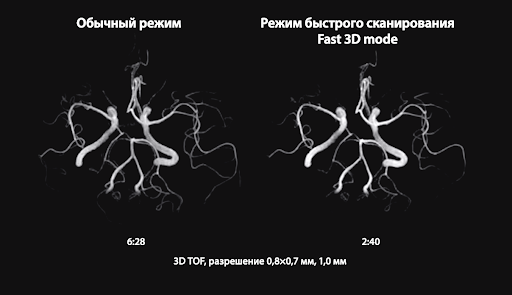

Режим Fast 3D mode сокращает время сканирования до 50% для изображений с разной контрастностью, сохраняя при этом их однородность и улучшая рабочий процесс.

Fast 3D